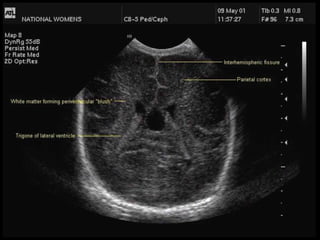

Angling further back cuts through the trigones of the lateral ventricles.

The choroid plexus fills the lateral ventricles in this view and is prominent in preterm infants.

Choroid plexus haemorrhage may be difficult to differentiate from bulky choroid.

The white matter around the lateral ventricles may appear quite echodense (bright) in this plane

and is sometimes called a "blush" or "flare".

Angling the transducer even more results in an image that slices above the lateral ventricles.

In this plane, the occipital cortex may be visualised.